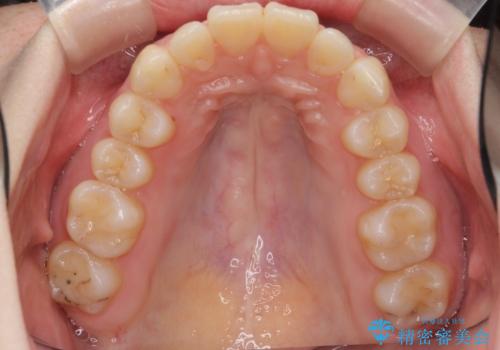

マウスピースで出っ歯感の改善

- 上の前歯が出ている感じを治したい、と矯正治療を希望され来院されました。

上顎歯列の突出感を改善すべくIPRを行い、下顎歯列を小さくすることで前歯の角度を大きく是正します、。

下顎歯列は元々前歯が1本少なく小さなアーチでしたが、下顎に合わせ上顎歯列もIPRを行い小さくすることで出っ歯感を大きく改善することが出来ました。